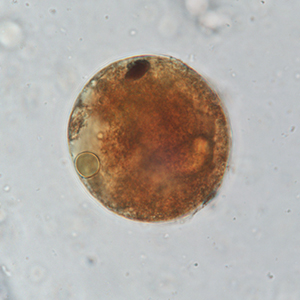

Le kyste est sphérique à ovoïde, à paroi épaisse, mesurant 50 à 100 μm de diamètre. Il présente un contenu granuleux, un macronucléus et micronucléus difficilement visibles (Strait et al., 2012). La coloration au Lugol permet de mettre en évidence certains organites qui apparaissent en brun sombre, de colorer la paroi en brun et l’intérieur du kyste en jaune.